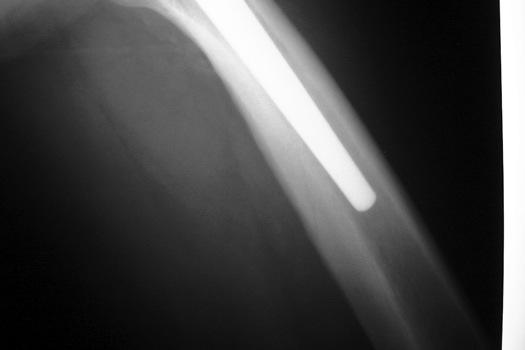

Intraoperative fracture of the proximal femur.

Intraoperative fracture of the femur at the tip of the femoral stem.